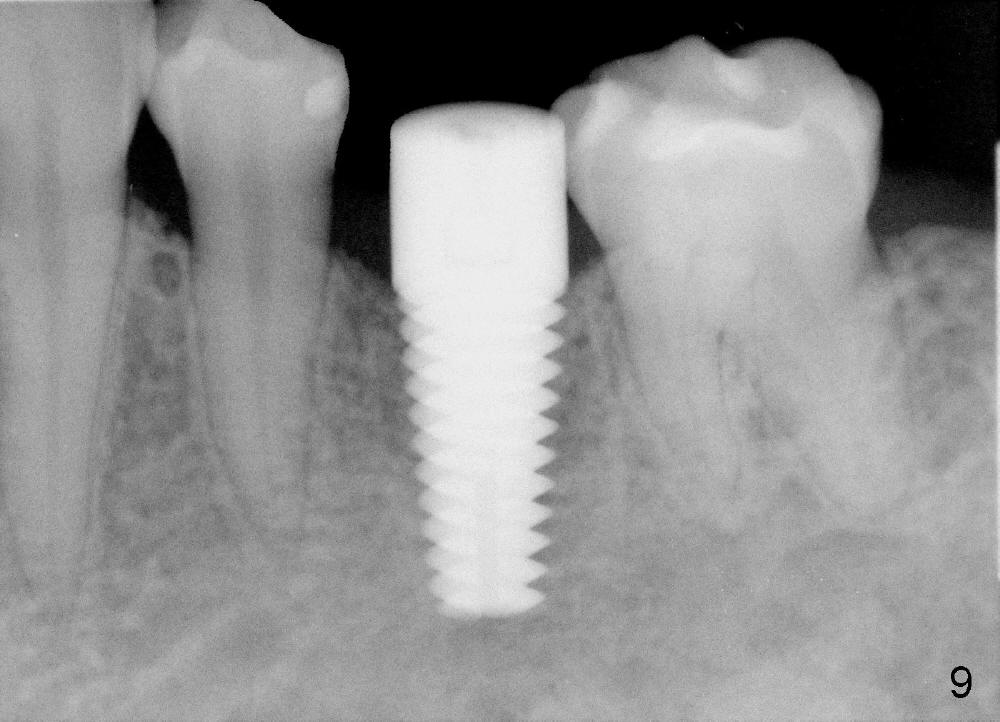

To avoid injury to the mental loop (Fig.2 dashed line), the depth of initial osteotomy is tightly controlled apical to the bottom of the socke.  Accurate measuring is the 2nd important measure to assure no or minimal neurological trauma. The wide socket (due to infection) allows to place an implant as wide as 7 mm.

Taking multiple intraop X-ray is also necessary for depth adjustment (Fig.3-5).  For example, when a 5x20 mm tap is inserted at the depth of 17 mm, it is close to the mental loop (Fig.4), whereas the binding to the bone is minimal.  So a larger implant is to be placed at a shallower depth (Fig.5: 6x17 mm with insertion torque >60 Ncm).  The shallower implant placement creates limited space for future abutment and crown (Fig.6,7).  A short abutment will be used and the implant margin will be prepared as low as possible.  As expected, the wound heals in a week (Fig.8).